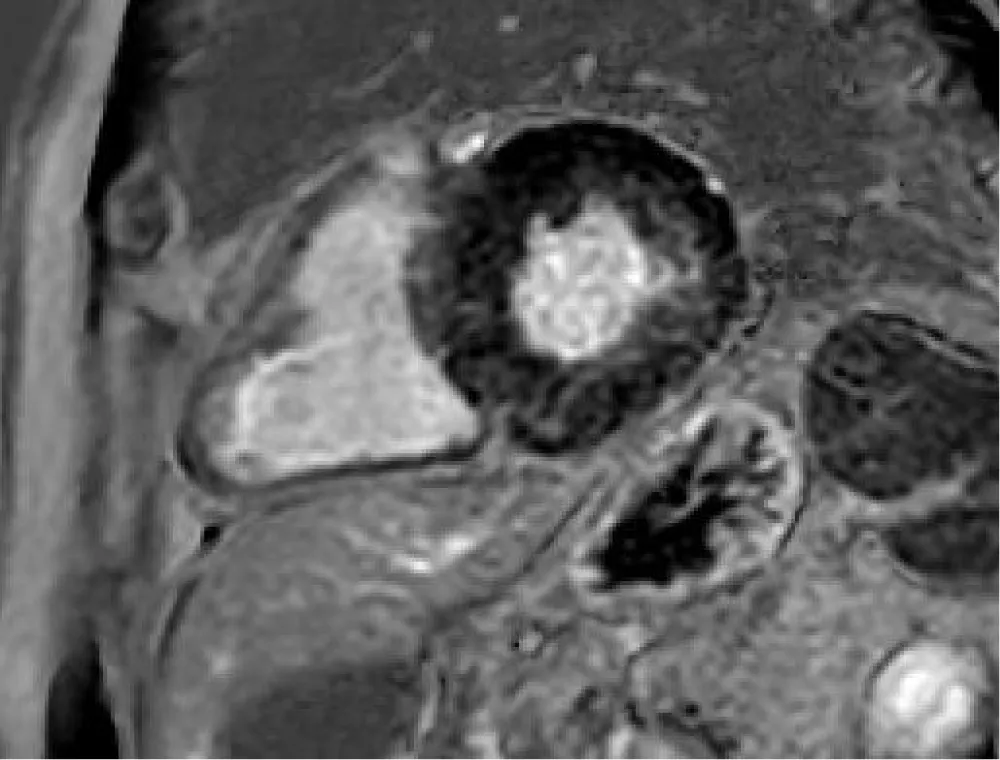

Normal myocardium has a hypointense signal, unlike the altered one which shows a hyperintense signal. The presence of Late Gadolinium Enhancement (LGE) is characteristic of fibrotic or scarred areas. In patients with AS, the LGE distribution is typically distributed in the infero-lateral wall of the myocardium, especially in the basal and middle segments (Figure 5).

Download Image

Figure 5: LGE sequences show mild hyperintensity signal in the mesocardial wall, especially along the inferolateral segment as fibrotic disarray.